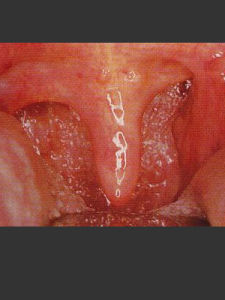

肥厚性咽炎主要表現為咽部黏膜充血肥厚,黏膜下有廣泛的結締組織及淋巴組織增生;其主要病理改變為黏膜瀰漫性充血肥厚,黏膜下有廣泛的結締組織及淋巴組織增生,咽後壁淋巴濾泡增生或毗連成片,咽側束呈條索狀隆起,是慢性單純性咽炎病情發展的結果。

咽部可有各種不同的感覺,如異物感、乾燥、灼熱、微痛等。咽分泌物增多、粘稠,故常有清嗓動作,吐白色粘痰。嚴重者可引起刺激性咳嗽及噁心、嘔吐、咽部檢查見黏膜瀰漫充血、血管擴張、色暗紅,附有少量粘稠分泌物。懸雍垂腫脹或鬆弛延長。

與慢性肥厚性咽炎相鑑別,後者黏膜充血肥厚,黏膜下有廣泛的結締組織及淋巴組織增生,形成咽後壁有顆粒狀隆起。若咽側索淋巴組織增生,則該處呈條索狀增厚。